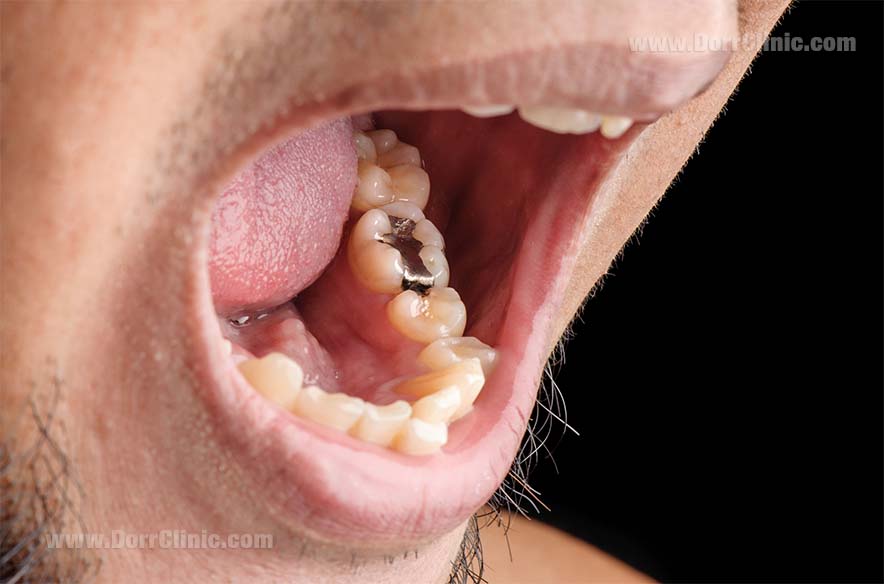

عکس دندان خراب

عکس دندان خراب. عکس دندان عصای دست دندان پزشک به هر شکل که عکس گرفته شود تصویر حاصل به دندان پزشک شما در تعیین اقدام مناسب کمک شایانی خواهد کرد. عکس سمت راست دندان با مینای خراب و عکس سمت چپ دندان سالم می باشد. مسواک زدن بهداشت دهان و دندان جویدن ناخن دندان قروچه درمان دندان. سلامت و بهداشت بیماری ها و راه درمان22 عادتی که دندان ها را خراب.

محفظة داخل دندان که حاوی رگهای خونی و عصب ها است پالپ نام دارد. خوردن بیش از حد در عارضه پرخوری عصبی باعث افزایش پوسیدگی دندان ها می شود اسیدهای قوی که در اثر استفراغ کردن از دهان خارج می شوند می توانند دندان ها را ضعیف و شکننده کنند این اسیدها همچنین باعث بوی بد دهان می. کشیدن دندان شیری رویش دندان شیری ریزش دندان شیری خراب شدن دندان شیری ریختن دندان شیری دندان شیری تعداد دندان شیری دندان شیری کودکان. من سی سالمه و اکثر دندان هام خراب شده یکی رو کشیدم دو تا رو پر کردم و دو تای دیگه رو هم دکتر گفت باید پر کنم و نیاز به عصب کشی دارند.